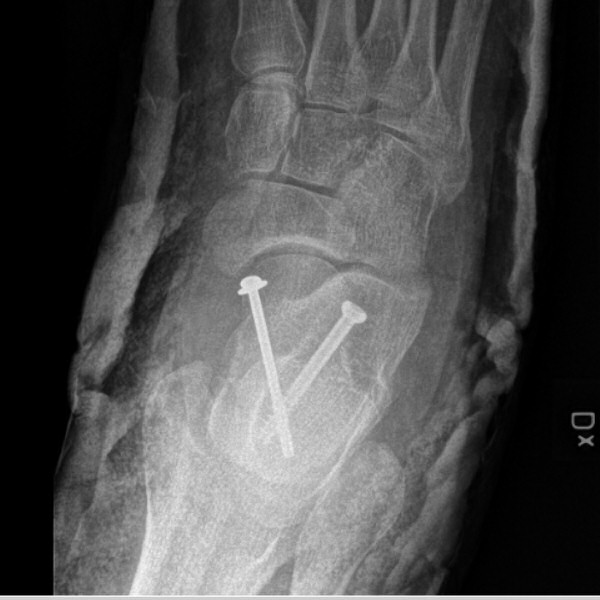

Talusfrakturen ovan fixerad med två skruvar

- Förbered snar operation med öppen reponering till exakt läge och skruvfixation med 2 skruvar, alt. 1 skruv och 1 stift.